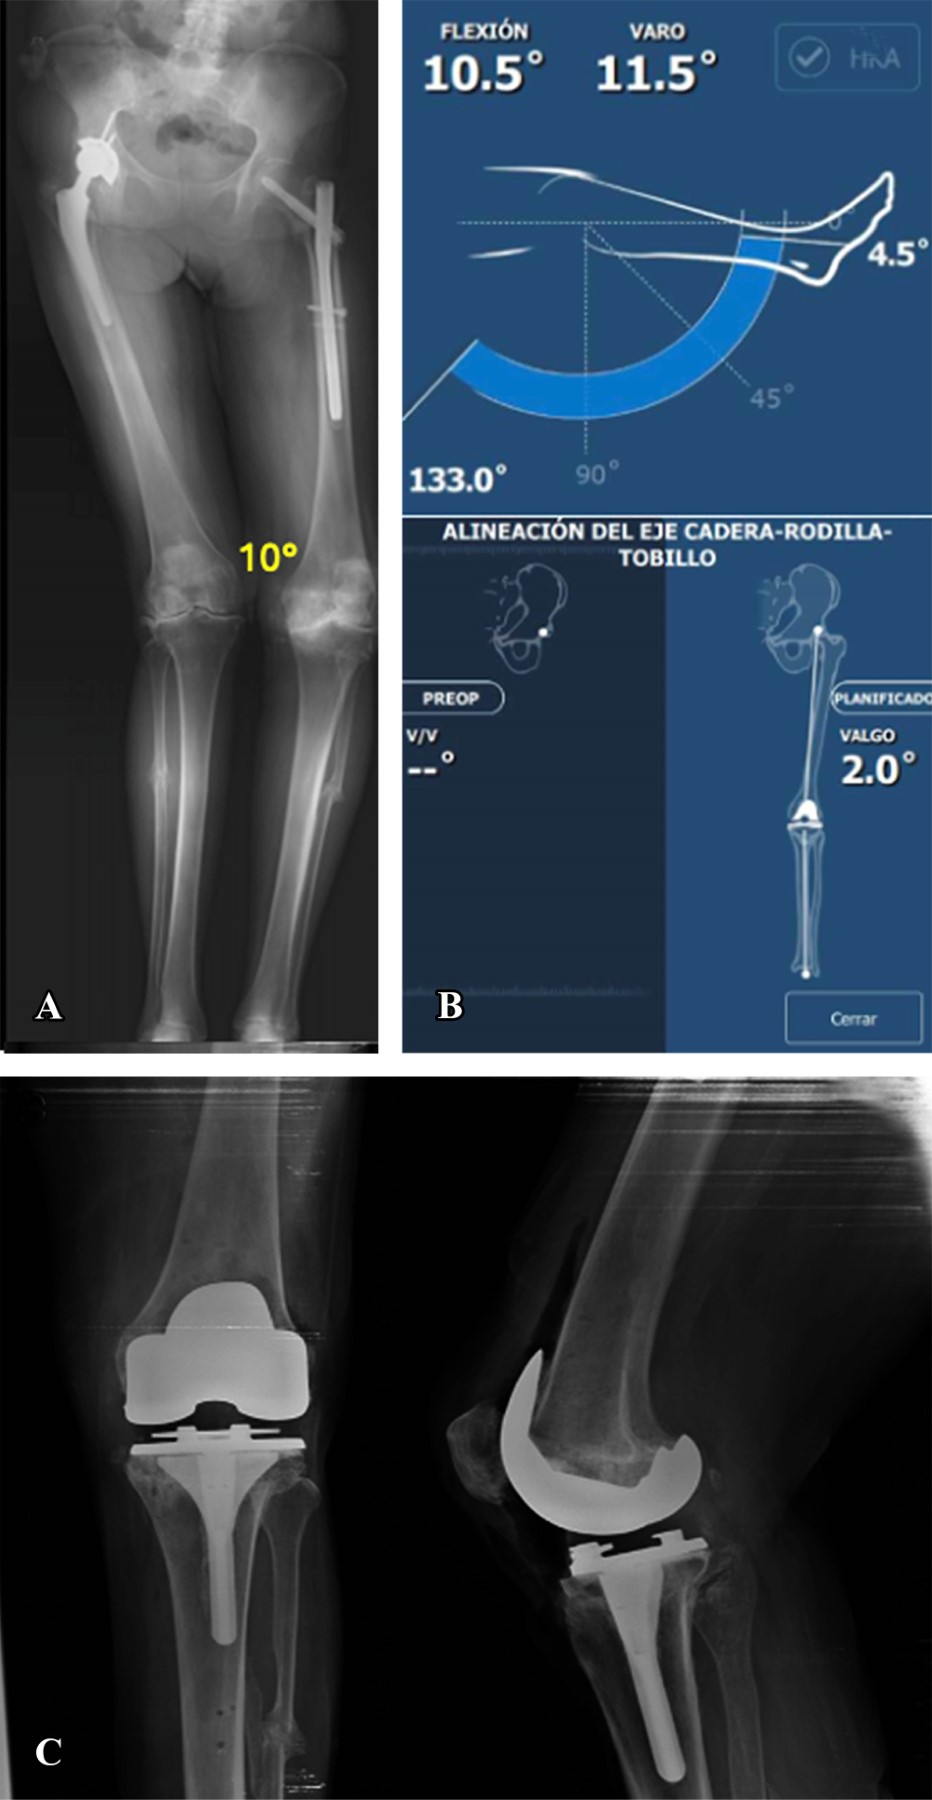

Dieciséis casos presentaron deformidad en valgo (Figuras 2 y 3) con un promedio de 11.88° de deformidad. En cuatro casos la alineación final fue en varo con un promedio 1.87°; en nueve la alineación final fue con un valgo promedio de 1.66° y en tres casos la alineación fue neutra. El cambio en los grados promedio de la serie entre la deformidad inicial y la alineación final fue estadísticamente significativo (p = 0.005) en el análisis de covarianza.

Figura 3